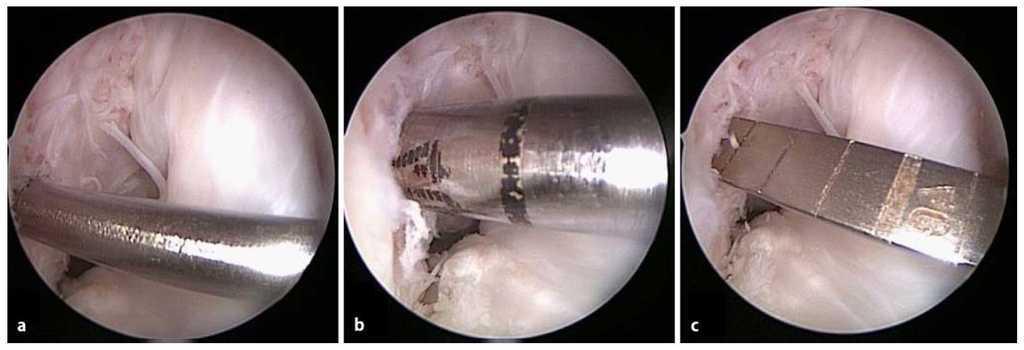

Fig. 19 8 Si la angulación del alambre es ligeramente errónea, la posición del túnel se puede corregir paso a paso realizando una perforación excéntrica hacia la posición deseada. Para ello debe perforarse primero la cavidad correcta con una broca delgada (a, b). A continuación se desplaza el alambre excéntricamente dentro del túnel y se prosigue con la perforación (c, d).